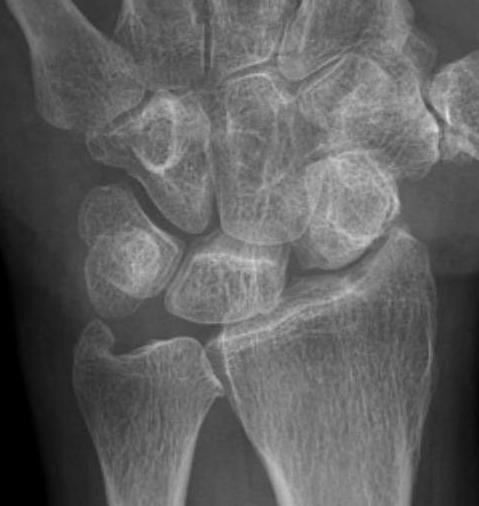

Scapho-lunate advanced collapse

- scapholunate disruption with flexion of scaphoid

- radioscaphoid arthritis with preservation of radiolunate joint

- descent of capitate into gap and progressive arthritic change

Most common cause of wrist OA

Watson and Ballet classification

Stage 1: Radial styloid / distal pole scaphoid degeneration

Stage 2: Radio-scaphoid degeneration

Stage 3: Capito-lunate degeneration

Stage 4: Pan carpal OA